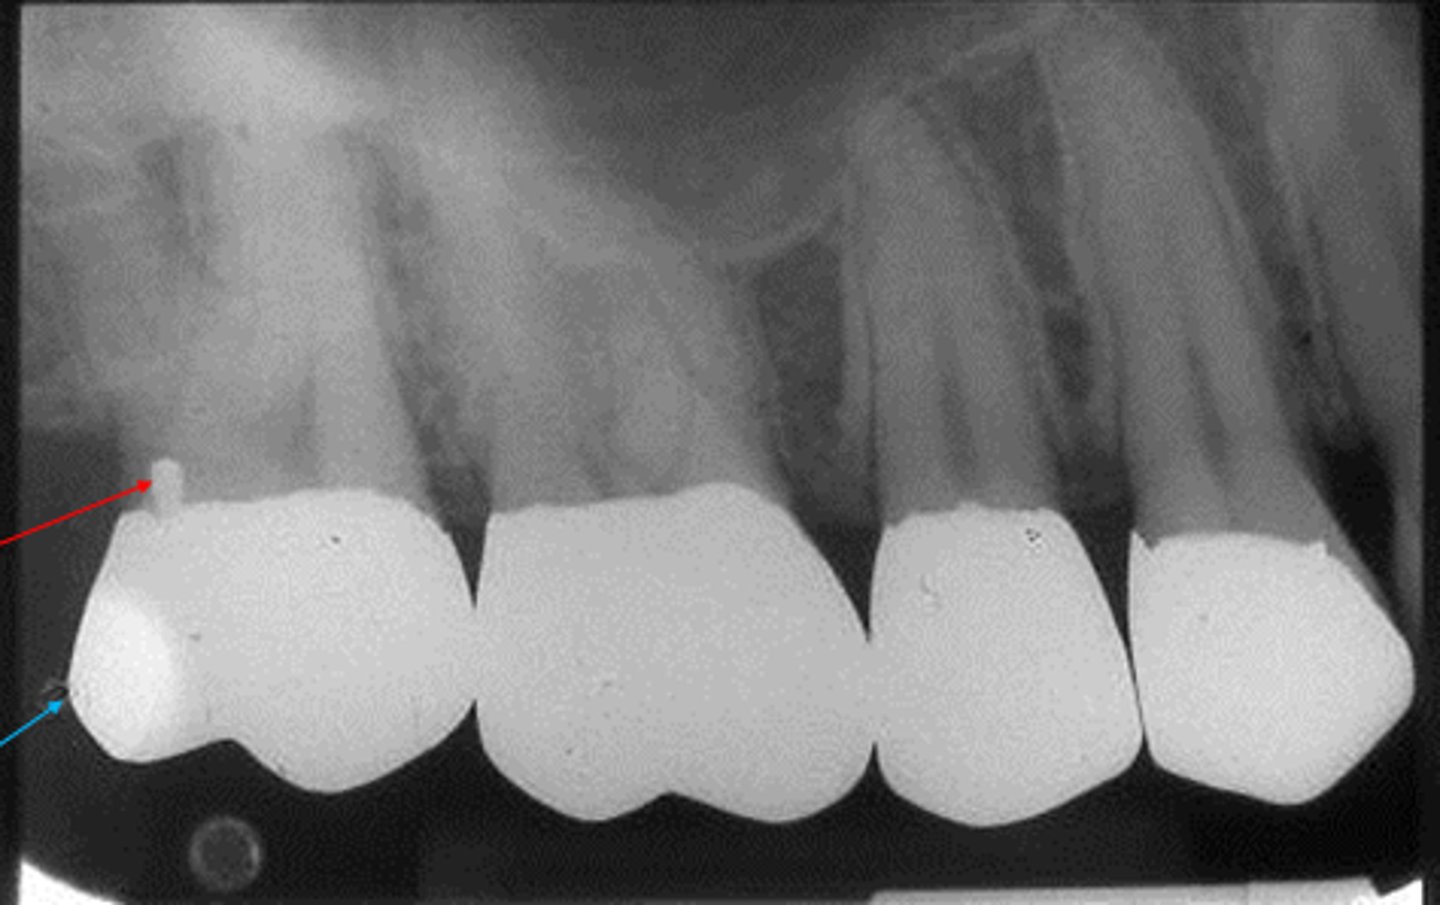

cone cut with beam alignment device (PA)

clear or white unexposed area

PID was not properly aligned with the beam alignment device

cone cut without beam alignment device (PA)

bisecting technique when a beam alignment device is not used

a clear or white unexposed area

PID was not directed at the center of the receptor

make sure PID is directed over the center of the receptor